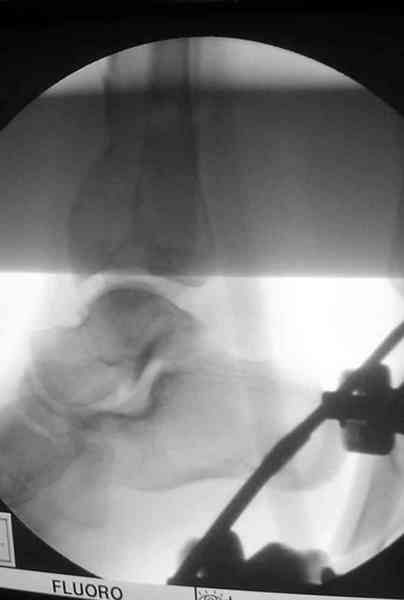

Снова приветствую вас, коллеги. К моменту вступления в обсуждение аксакалов, операция была, увы, выполнена(31.10.07.) Начали с доступа к наружной лодыжке, произвели ее фиксацию спицами, развернули кусок заднего края, наложили дистрактор, затем произвели дистракцию, фиксацию спицами дистального эпиметафиза б/бк,Рентгено-контроль. синтез наружной лодыжки 1/3пластиной. из двух коротких разрезов сформирован канал под медиальную тибиальную пластину LCP. Края ран ушиты без натяжения. Прочувствовать жесткость фиксации винтами с угловой стабильностью не удалось, поэтому дистрактор оставлен на энное время.

На представленных R-снимках не окончательный вид после остеосинтеза. Дистальная опора давила на стопу, пришлось ее сместить проксимально, в рез-те чего, она закрыла щель сустава, последние снимки не информативны.